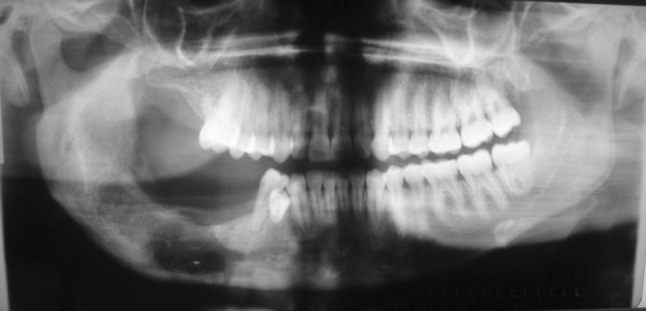

The panoramic radiographours revealed a large irregular radiopaque mass extending anteriorly from the 46 to just below the sigmoid notch posteriorly, inferiorly to just above the lower border of the mandible and superiorly to beyond the alveolar crest. The lesion was surrounded by a distinct radiolucent rim. An impacted molar tooth was located just above the lower border in line with the 46 region (Fig. 3). Further history taking revealed that this patient had previously attended our department in 2004 for the same complaint, but subsequently defaulted. She was lost to follow up until her return in 2008. The panoramic radiograph taken in 2004 showed a large radiopacity extending from the distal aspect of the 46 to the mid-ramus posteriorly and the lower border of the mandible inferiorly. There was an impacted molar at the lower border of the mandible. The lesion was surrounded by a radiolucent border, which seemed to be more pronounced in the ramus (Fig. 4). A comparison of the panoramic radiograph taken in 2004 and 2008 clearly illustrates the changes in the lesion over a 4 year period as it sequestrated into the oral cavity. In 2004 the lesion appeared to be less dense, smaller and positioned below the occlusal plane. The radiolucent rim was also narrowed. In 2008 the lesion appeared to have grown in size. It was more dense, probably an indication of its advanced stage of maturity. It had also moved to beyond the occlusal plane. The radiolucent rim was wider, and the impacted tooth seemed to have moved occlusally with an enlarged follicle surrounding its crown. The inferior alveolar canal was displaced inferiorly towards the lower border of the mandible. The radiographs of 2004 and 2008 did not show root resorption.

Fig. 4.

Panoramic radiograph (2004); the extension of the radiopaque lesion into the ramus and the impacted first molar above the inferior border of the mandible is clearly visible. The lesion is surrounded by a radiolucent border, which seems to be more pronounced in the area of the ramus